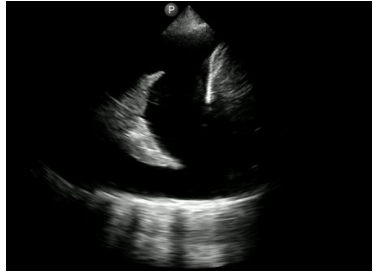

Imagem de ultrassonografia torácica com visualização de estrutura hiperecogênica triangular, com presença de regiões mais e menos hiperecogênicas de maneira intercalada, cercada por material homogeneamente hipoecogênico.

Assinale a opção que descreve o achado.